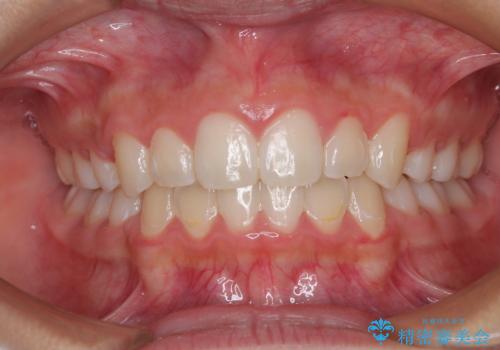

舌の突出癖の影響もあり、非抜歯矯正で治療開始したものの口元が突出し、唇が閉じにくくなってしまったため、途中で第一小臼歯4本を抜歯ししました。

口元の突出感のない、すっきりとした仕上がりとなりました。